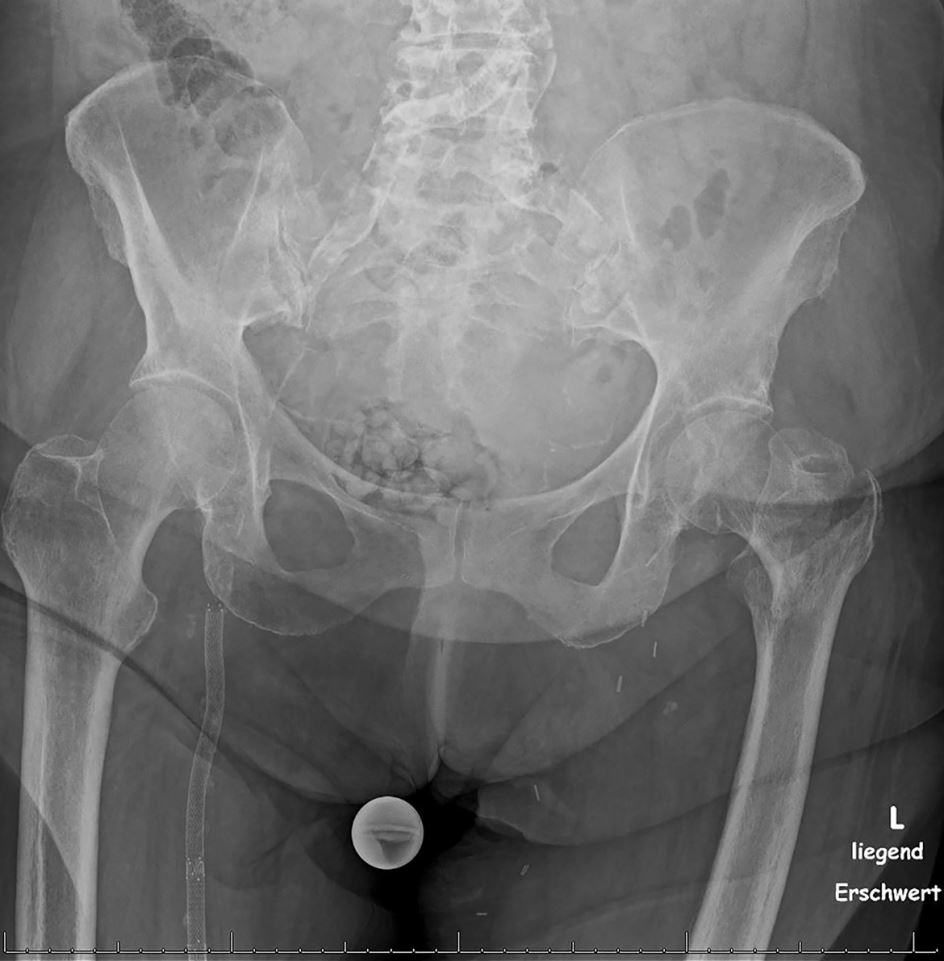

Eine 84 Jahre alte Patientin war zu Hause über einen Teppich gestolpert und gestürzt. Der sofort einsetzende Schmerz war so stark, dass sie ihre linke Hüfte nicht mehr bewegen konnte. Sie wurde in die Unfallambulanz eingeliefert. Bei der körperlichen Untersuchung fiel sofort auf, dass ihr linkes Bein verkürzt und nach außen rotiert war.

Nach außen rotierter Fuß nach Oberschenkelhalsfraktur/© A. Schuh, Kleinkind rennt draußen, während es in die Luft zeigt/© William / Adobe Stock, Teaserbild HPV-Impfung für Erwachsene – eine Rechnung die aufgeht!/© syedfahadghazanfar / shutterstock, Neuer Inhalt/© MKC / shutterstock, Teaserbild OA Wörwag Zink/© Tondone | AdobeStock